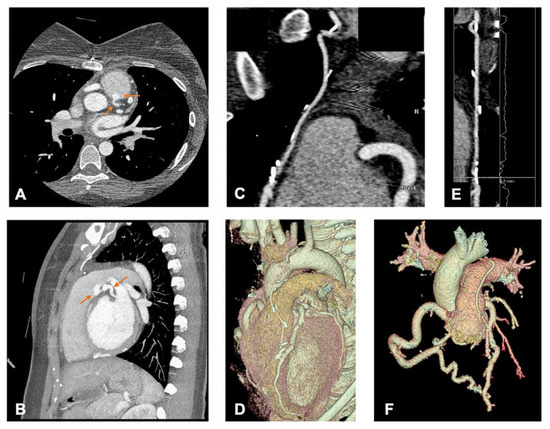

Coronary computed tomography (CT) angiography revealed a patent LIMA to LAD bypass, ectasia of right coronary artery and a suture dehiscence with a recanalisation of the left coronary artery ostium with signs of arterial flow from the left main to the pulmonary trunk (Figure 1) The patient underwent new cardiac surgery, and an ostium closure was performed with a polypropylene suture in an autologous pericardium patch. The patient was discharged from the hospital and after a 6-month follow-up remained asymptomatic.

Figure 1. Axial and sagittal coronary computed tomography angiography images showing an anomalous left coronary artery from the pulmonary artery with signs of contrast flowing to the pulmonary artery suggestive of a left-to-right shunt (A and B). A patent left internal mammary artery to left anterior descending artery bypass can be observed in multiplanar reconstructed (C and E) and volume rendered (D) images. Coronary ectasia is also evident (F) as a result of a compensatory mechanism and a high-flow state originated by a coronary steal phenomenon. In this situation, blood is diverted from the right coronary artery and collateral circulation to the left coronary artery and the pulmonary trunk. In order to avoid myocardial ischaemia, the coronary arteries dilate to allow an increase of blood flow.

Bland-Garland-White syndrome rarely presents in adults and data regarding the surgical strategy is limited and controversial [1,2,3]. In this patient, the heart team decided to perform ostium closure and LIMA bypass rather than reimplantation, as coronary mobilisation would not be adequately performed. Chest pain after this surgical correction may have several causes. Cardiovascular CT has high spatial resolution and rapid acquisition time, being the preferred technique for the evaluation of coronary artery anomalies and allowing the assessment of high-risk anatomy features [4]. In this particular case, cardiovascular CT allowed the identification of an ostium recanalisation and excluded other important causes of thoracic pain, including bypass failure.